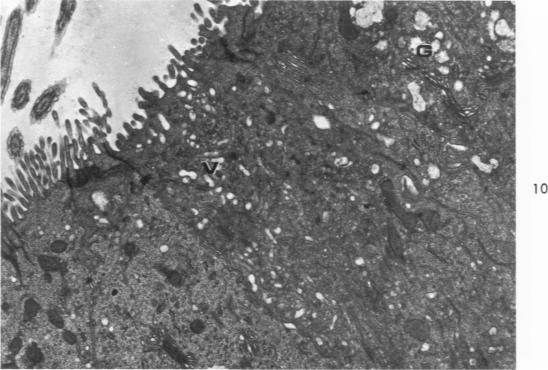

The major bronchi of swine, a dog and rabbits were examined with a scanning electron microscope and the fine structure of the openings of bronchial glands were studied three-dimensionally. The smallest areas of squamous metaplasia involved the duct openings. By examining serial sections with the light and transmission electron microscopes these early lesions were found localized at the opening of the bronchial gland duct. Cells intermediate to goblet and squamous cells were present in these lesions. Squamous metaplasia starting at this particular location is probably common and metaplasia can be an intracellular process.

用扫描电子显微镜检查了猪、狗和兔子的主支气管,并对支气管腺开口的精细结构进行了三维研究。鳞状化生面积最小的区域涉及导管开口。通过光学显微镜和透射电子显微镜检查连续切片,发现这些早期病变局限于支气管腺导管开口处。在这些病变中存在介于杯状细胞和鳞状细胞之间的细胞。从这个特定位置开始的鳞状化生可能很常见,并且化生可能是一个细胞内过程。